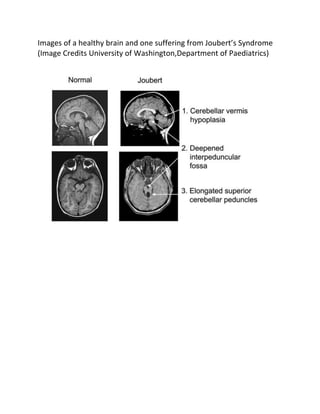

The following image from brains of healthy individuals and those

suffering from Joubert’s syndrome might give an idea of how the

various regions in the brain are malformed in this particular

neurological disorder.

Images of a healthy brain and one suffering from Joubert’s Syndrome

(Image Credits University of Washington,Department of Paediatrics)